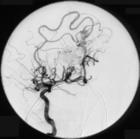

动静脉畸形出血最常用的诊断方法是上消化道内镜,结肠镜,小肠镜,术中内镜或内脏造影(随出血部位而定).通常选择性血管造影或简单的剖腹探查常不能发现动静脉畸形,内镜下是否明显常取决于消化道粘膜的微循环,后者常受低血容量状态,麻醉及心排出量降低等因素的影响.锝标记的红细胞扫描较不敏感,诊断价值较低.

患者常大于60岁,表现为鲜血便或紫红色便,常有长期的反复无痛性胃肠道出血,并经多种检查(包括剖腹术)未见特殊异常.出血可表现为急性或大量出血,而无低血压表现.虽然内镜或肠系膜造影可有假阳性,却是最好的诊断方法.